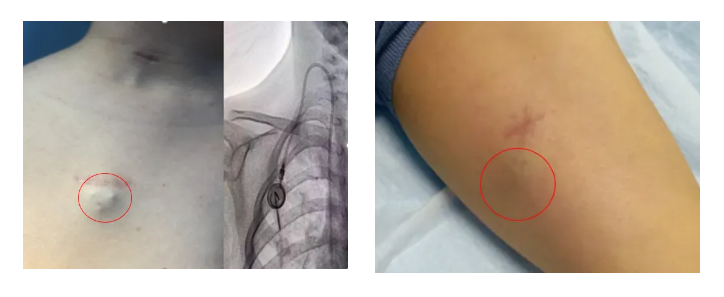

輸液港,即完全植入式輸液港(PORT),是一種可完全植入皮下并長期留存體內(nèi)的輸液裝置,主要由注射座(又稱港體)和硅膠導(dǎo)管兩部分組成。注射座被埋植于胸部皮下,導(dǎo)管則連接到上腔靜脈,形成一個閉合的靜脈輸液系統(tǒng)。其常見類型有手臂輸液港與胸壁輸液港。

67b591bc847ed.jpg